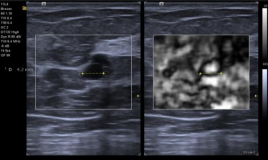

SieScape Panoramic Imaging(SieScape)宽景成像: 对于较大器官或病灶的观察,借助宽景成像,利用实时高分辨率灰度成像获得全景图像,方便观察靶目标的整体大小、形态以及毗邻位置,可在全景图像上进行测量、旋转等操作降低拼图测量产生的误差,且最长扫描长度>2 米,角度可达 180°,可应用与所有线阵及凸阵探头,应用领域广泛。